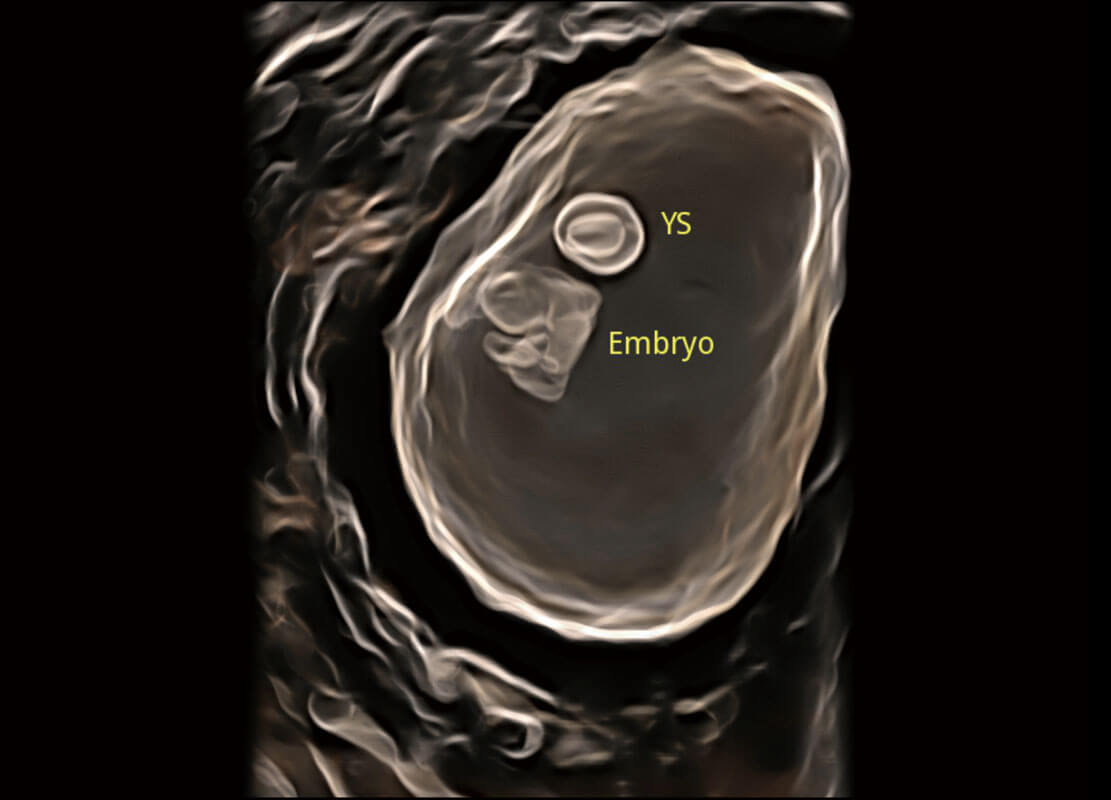

P60在胎兒早孕期超聲篩查中為您帶來優(yōu)異的圖像質(zhì)量。

高分辨率容積成像-早孕胎兒

光影成像-孕囊